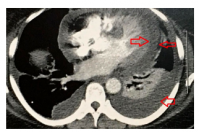

A 49-year-old female patient was admitted with recurrent episodes of fever (39.4°C), transient rash, weight loss, sore throats, and polyarthritis of wrists, knees, metacarpophalangeal and proximal interphalangeal joints in November 2012. No splenomegaly, hepatomegaly or lymphadenopathy was detected. Laboratory tests revealed a hemoglobin of 11.9 g/dL (12-16 g/dL), white blood cell count of 12,800 cells/mm3 (4,000-10,000 cells/mm3), platelets of 798,000/μL (150,000-450,000/μL), aspartate aminotransferase of 62 U/L, alanine aminotransferase of 86 U/L, C-reactive protein (CRP) of 44.1 mg/dL (<5 mg/dL), erythrocyte sedimentation rate (ESR) of 72 mm/1st h (<20 mm/1st h), acid alpha1-glycoprotein of 279 mg/ dL (50-120 mg/dL), and ferritin of 3,465 ng/ mL (11-306 ng/mL). Antinuclear antibodies, rheumatoid factor, anti-cyclic citrullinated peptide, anti-double-stranded deoxyribonucleic acid, anti- Ro/SSA, anti-La/SSB, anti-U1-ribonucleoprotein, anti-Schistosoma mansoni, and human leukocyte antigen-B27 were negative. Serology for infectious disease were also negative. Thoracic and abdominal computed tomography (CT) showed mediastinal lymphadenopathy, pleural effusion, and mild splenomegaly. A diagnosis of AOSD was established.[4] During the investigation, the patient experienced severe pleuritic pain, dyspnea and was hospitalized in another province. X-ray demonstrated a large left pleural effusion, and the CT showed a pericardial and a large left pleural effusion (Figure 1). Lung parenchyma was not involved. A thoracocentesis was performed and the liquid was an exudate, no infectious agent was identified in the cultures and polymerase chain reaction testing. The pleural biopsy showed a chronic unspecific inflammatory process. During the hospital stay, difficulties in weaning her off the thoracic draining tube were encountered due to high volume production of pleural effusion. Based on the decision of the multidisciplinary team, pleurodesis was performed. The procedure was performed via a medical thoracoscopy after complete removal of pleural fluid, and talc powder was sprayed by the use of an atomizer, with no intercurrent problem. Upon discharge, prednisone 60 mg/day was initiated. A marked improvement of all clinical and laboratory picture was noticed. The patient became asymptomatic with normalized ESR, CRP, and acid alpha1glycoprotein, transaminases, and ferritin (87 ng/mL) levels. Thoracic X-ray showed the absence of pleural effusion and echocardiography revealed no pericardial effusion. Hydroxychloroquine (HCQ) 400 mg/day and methotrexate 15 mg/week were added to the treatment. She is currently asymptomatic with stable thoracic X-ray using HCQ and methotrexate. A written informed consent was obtained from the patient for all diagnostic and therapeutic procedures.